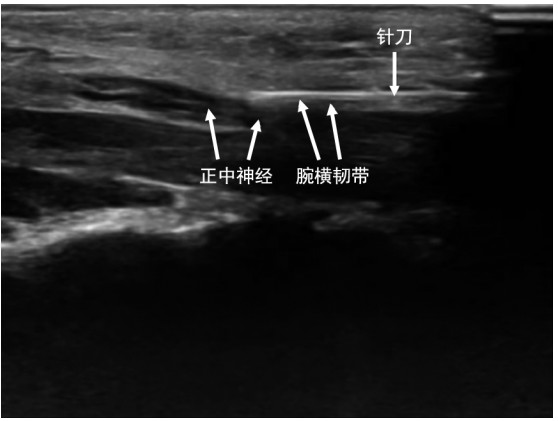

•   Objective  Ultrasound visualization provides technical support for the precise application of acupotomy in treatment of carpal tunnel syndrome (CTS). This study explores the application advantages of ultrasound-guided acupotomy in the treatment of CTS compared with traditional blind acupotomy.  Methods  A total of 94 patients with CTS who received acupotomy therapy at the Department of Rehabilitation in Dongyang People ' s hospital from January 2022 to February 2025 were enrolled. According to different treatment methods, they were divided into a control group (receiving traditional blind acupotomy therapy) and an ultrasound group (receiving ultrasound-guided acupotomy therapy), with 47 cases in each group. They were both received twice treatment sessions and followed up for 4 weeks. Pain visual analogue scale (VAS) scores, ultrasonic measurements [thickness of transverse carpal ligament (TTCL), median nerve cross-sectional area (CSA), and anterior and posterior diameter of median nerve (D) in the cross section of uncinate bone], EMG measurements [median nerve end motor latency (DML), median sensory nerve conduction velocity (SNCV), and compound muscle action potential (CMAP)] were compared between the two groups before and after treatment. Pre- and post-treatment comparisons were performed to evaluate the therapeutic efficacy and the complications.  Results  The VAS scores of numbness and pain in daytime and nighttime after treatment were lower than those before treatment (P < 0.05). In addition, the daytime [(2.04±0.61) points vs. (2.61±0.70) points] and nighttime numbness VAS scores [(2.23±0.64) points vs. (2.87±0.75) points] of the ultrasound group were lower than those of the control group (P < 0.05), respectively. After treatment, TTCL, CSA, D, and DML were significantly decreased, while SNCV and CMAP were higher than before treatment (P < 0.05). Improvements were more pronounced in the ultrasound group than in the control group, while SNCV and CMAP were higher than control group (P < 0.05). The therapeutic grade composition of the ultrasound group was better than that of the control group (Z=4.506, P=0.003), with no significant difference in the complication rates between the two groups (P>0.05).  Conclusion  Compared with traditional blind acupotomy, ultrasound-guided acupotomy provides better symptoms relief of numbness and pain in CTS patients, improves the ultrasonography and EMG indicators, and improves clinical efficacy.